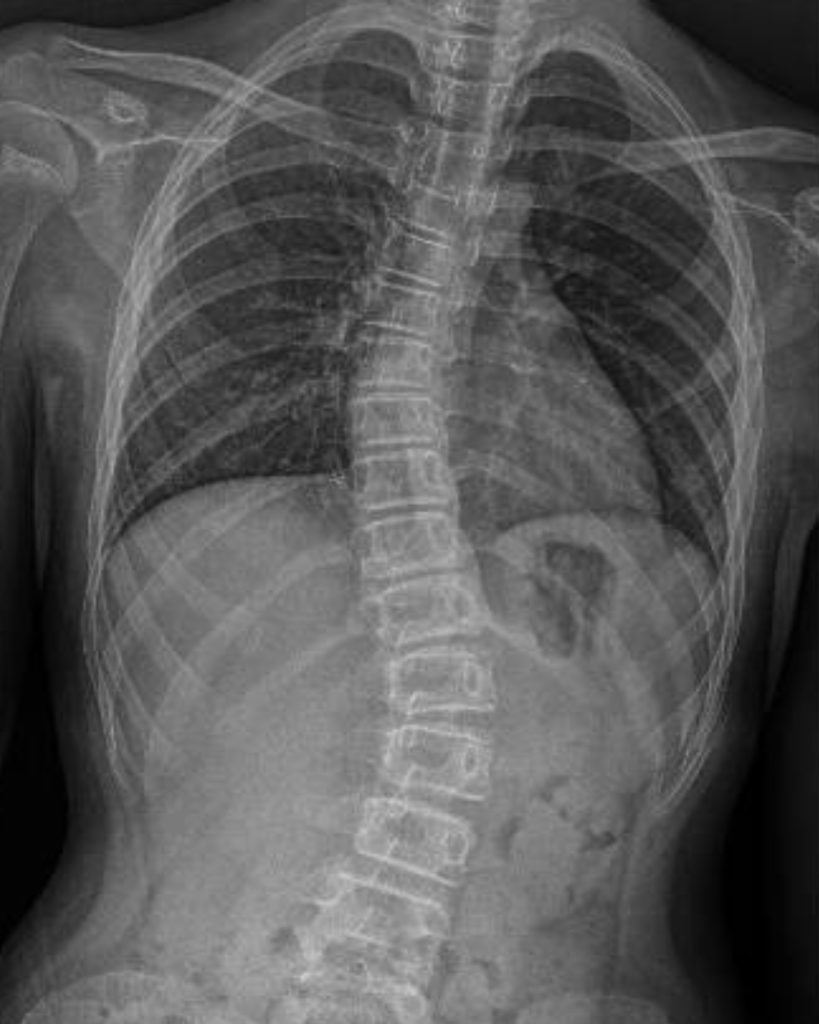

Scoliosis merujuk kepada kelengkungan tulang belakang secara lateral yang tidak normal, dan sering disertai dengan putaran vertebra. Kebanyakan kes dikenal pasti ketika usia remaja dan tahap keterukan berbeza – dari kelengkungan ringan sehinggalah melebihi 45 darjah yang memerlukan pembetulan pembedahan.

Namun, tulang belakang bukanlah struktur yang terasing – ia berhubung secara langsung dengan otot, organ penting, dan sistem tubuh lain. Menurut Dr Tan Jin Aun, Pakar Perunding Ortopedik dan Pakar Bedah Tulang Belakang di SMCD, kesan kesihatan sekunder biasanya timbul apabila kelengkungan mencecah 70 hingga 100 darjah. Pada tahap ini, ia boleh menjejaskan fungsi paru-paru atau sistem penghadaman, bergantung pada lokasi dan jenis scoliosis.

Menurut Dr Deepak A/L Ajit Singh, Pakar Bedah Ortopedik (Pakar Pembedahan Tulang Belakang dan Pengurusan Sakit Intervensi), proses diagnosis biasanya bermula dengan pemeriksaan klinikal dan radiograf tulang belakang.

Satu imbasan radiograf ringkas selalunya cukup untuk menentukan sama ada scoliosis wujud. Jika dikesan awal, rawatan yang sesuai boleh dirancang – sama ada pemantauan, alat sokongan, atau pembetulan melalui pembedahan.